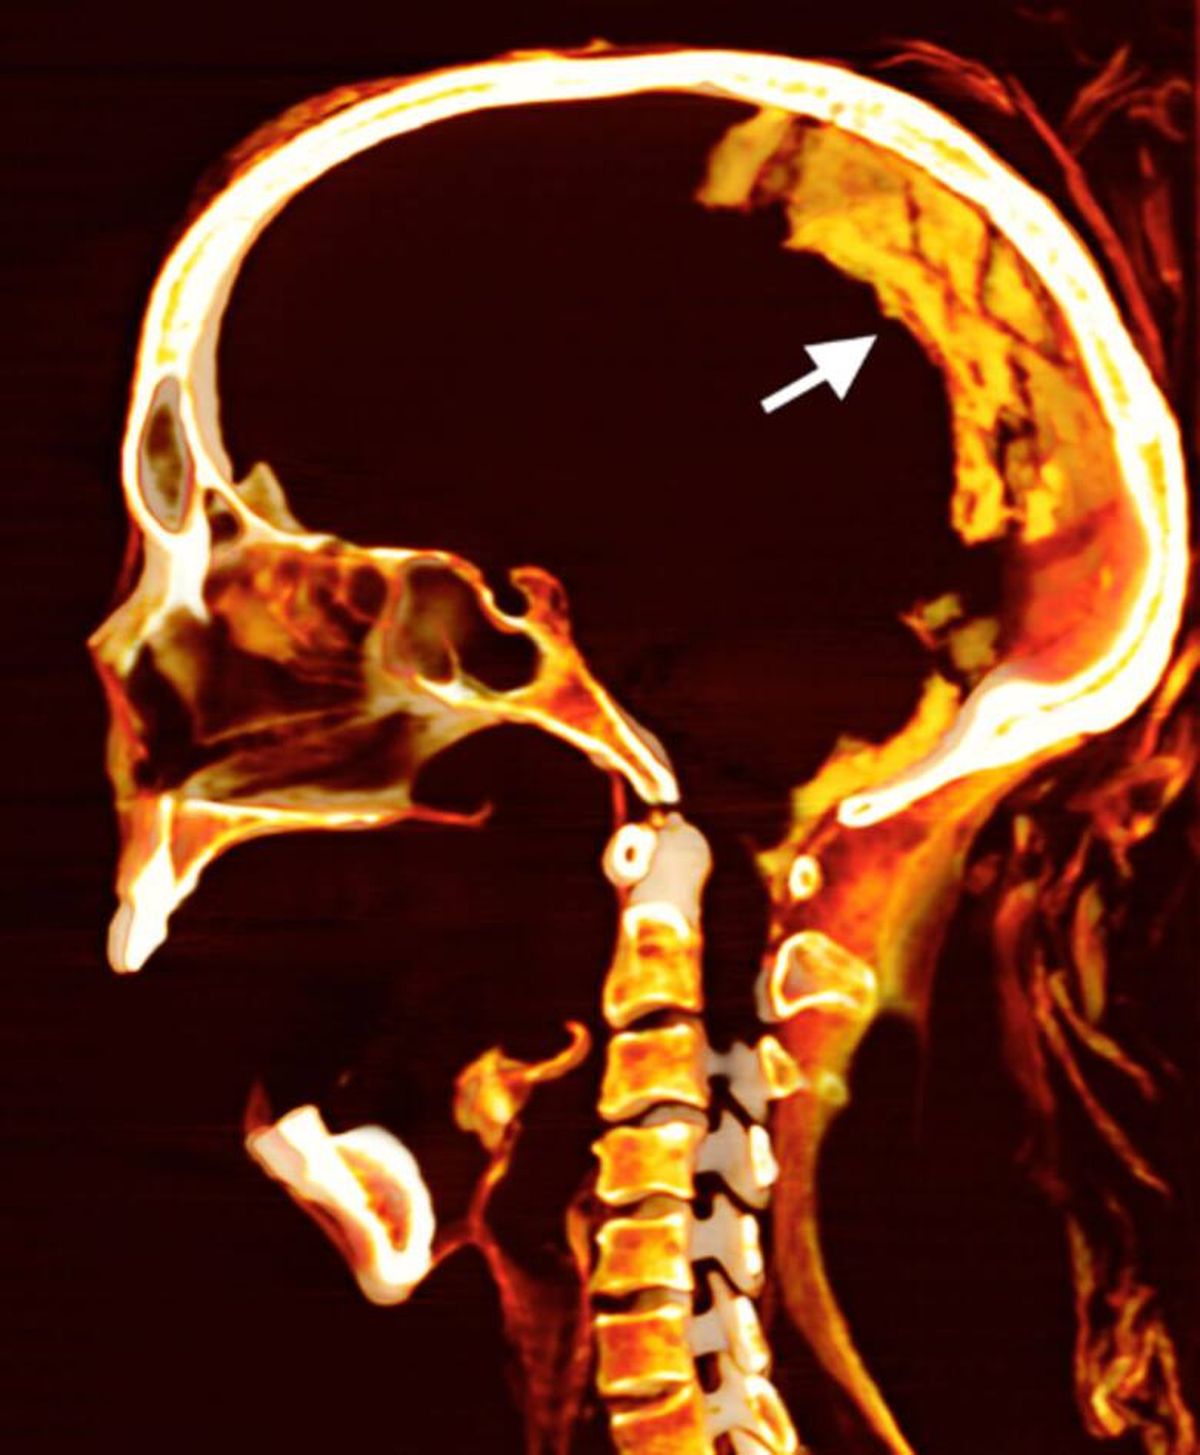

En la revista Frontiers in Medicine se reveló un importante trabajo que dio lugar a nuevos datos acerca de un misterio que llevaba años sin ser aclarado. Se trata de un estudio realizado con avanzadas técnicas de imagen que concluyeron en una "autopsia virtual" de la famosa momia de Egipto.

Liderado por la Dra Sahar Saleem, el equipo de investigación reveló que la momia encontró la muerte a los 48 años de edad y se produjo hace 3500 años durante el periodo del Nuevo Reino.

Por otro lado, a diferencia de otras momias de ese entonces, esta mujer conservaba tanto sus vísceras como su cerebro intacto. Es así que llevó a los especialistas a plantearse técnicas de embalsamamiento diferentes a las ya conocidas.

En paralelo a esto, desde la agencia Reuters aseguraron que la doctora comentó que la momia gritona falleció en un estado de agonía extrema. De acuerdo a la información que se sabe sobre medicina, una gran agonía podría haber provocado un espasmo cadavérico que terminó contrayendo sus músculos y dándole así la expresión facial que tanto la caracteriza.